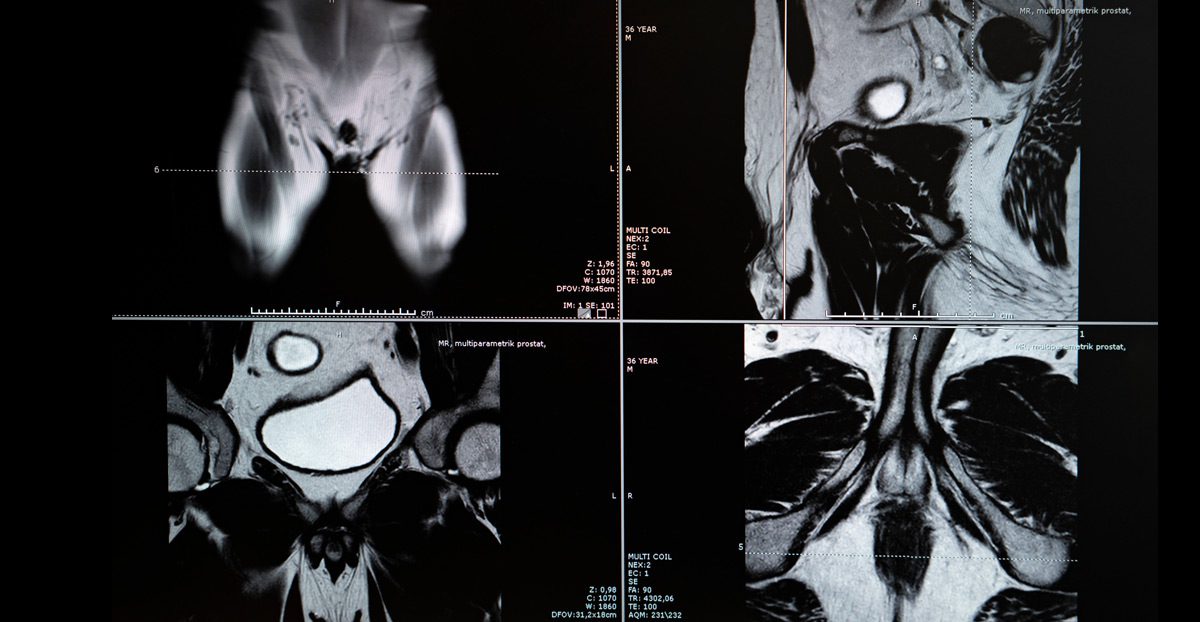

- MRI imaging identifies lesions suspicious for prostate cancer

- MRI-ultrasound fusion may be used to precisely target suspicious areas

- MRI-Guided Precision: Enables targeted biopsy of suspicious lesions